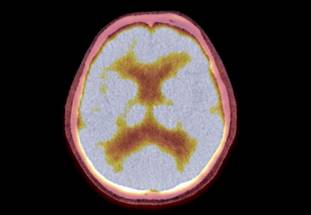

Brain metastases are the most prevalent adult central nervous system tumors, with 20% to 30% of cases resulting from breast cancer patients, particularly those with triple negative and HER2 amplified disease. Managing breast cancer metastases in the brain is challenging, with only 20% of patients with breast cancer brain metastases surviving beyond five years.